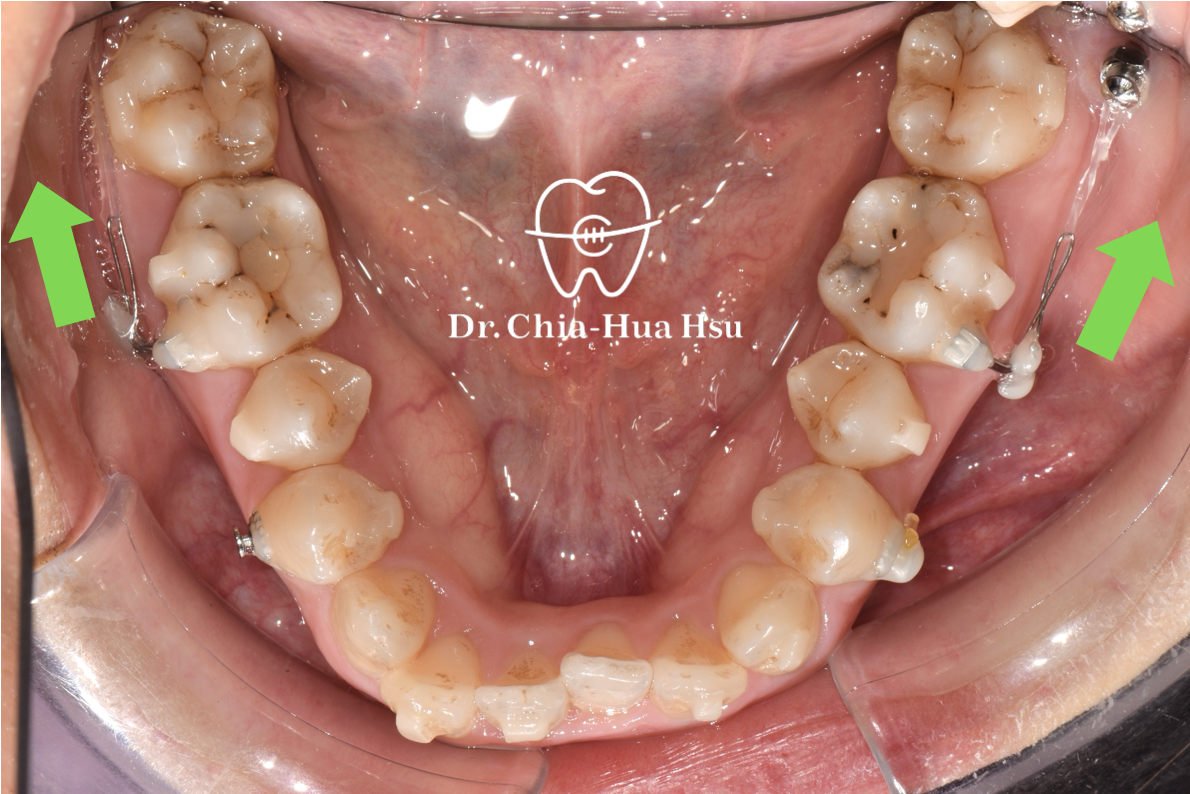

- 外觀與尺寸:矯正骨釘非常小,形狀類似迷你螺絲,一般長度約 6–12 毫米、直徑 1.5–2 毫米。

- 骨釘的作用:矯正骨釘就像在骨頭裡多加了一個「超穩固的固定點」,醫師能利用它施加更精準、穩定的力量,幫助牙齒移動到正確位置,而不會因互相牽制而偏移。

- 當牙齒的移動方向或距離較困難且複雜的時候,矯正骨釘就派上用場。其主要用途包括:

- 輔助隱形牙套施力,縮短療程時間

- 在牙齒缺損區缺乏支點時提供穩定施力

- 骨釘的最大優點,是能大幅提升牙齒移動的控制力與精準度,不僅有助於加快療程速度,還可能減少拔牙或手術的必要性。對於某些複雜的矯正情況,它更是不可或缺的重要輔助工具。